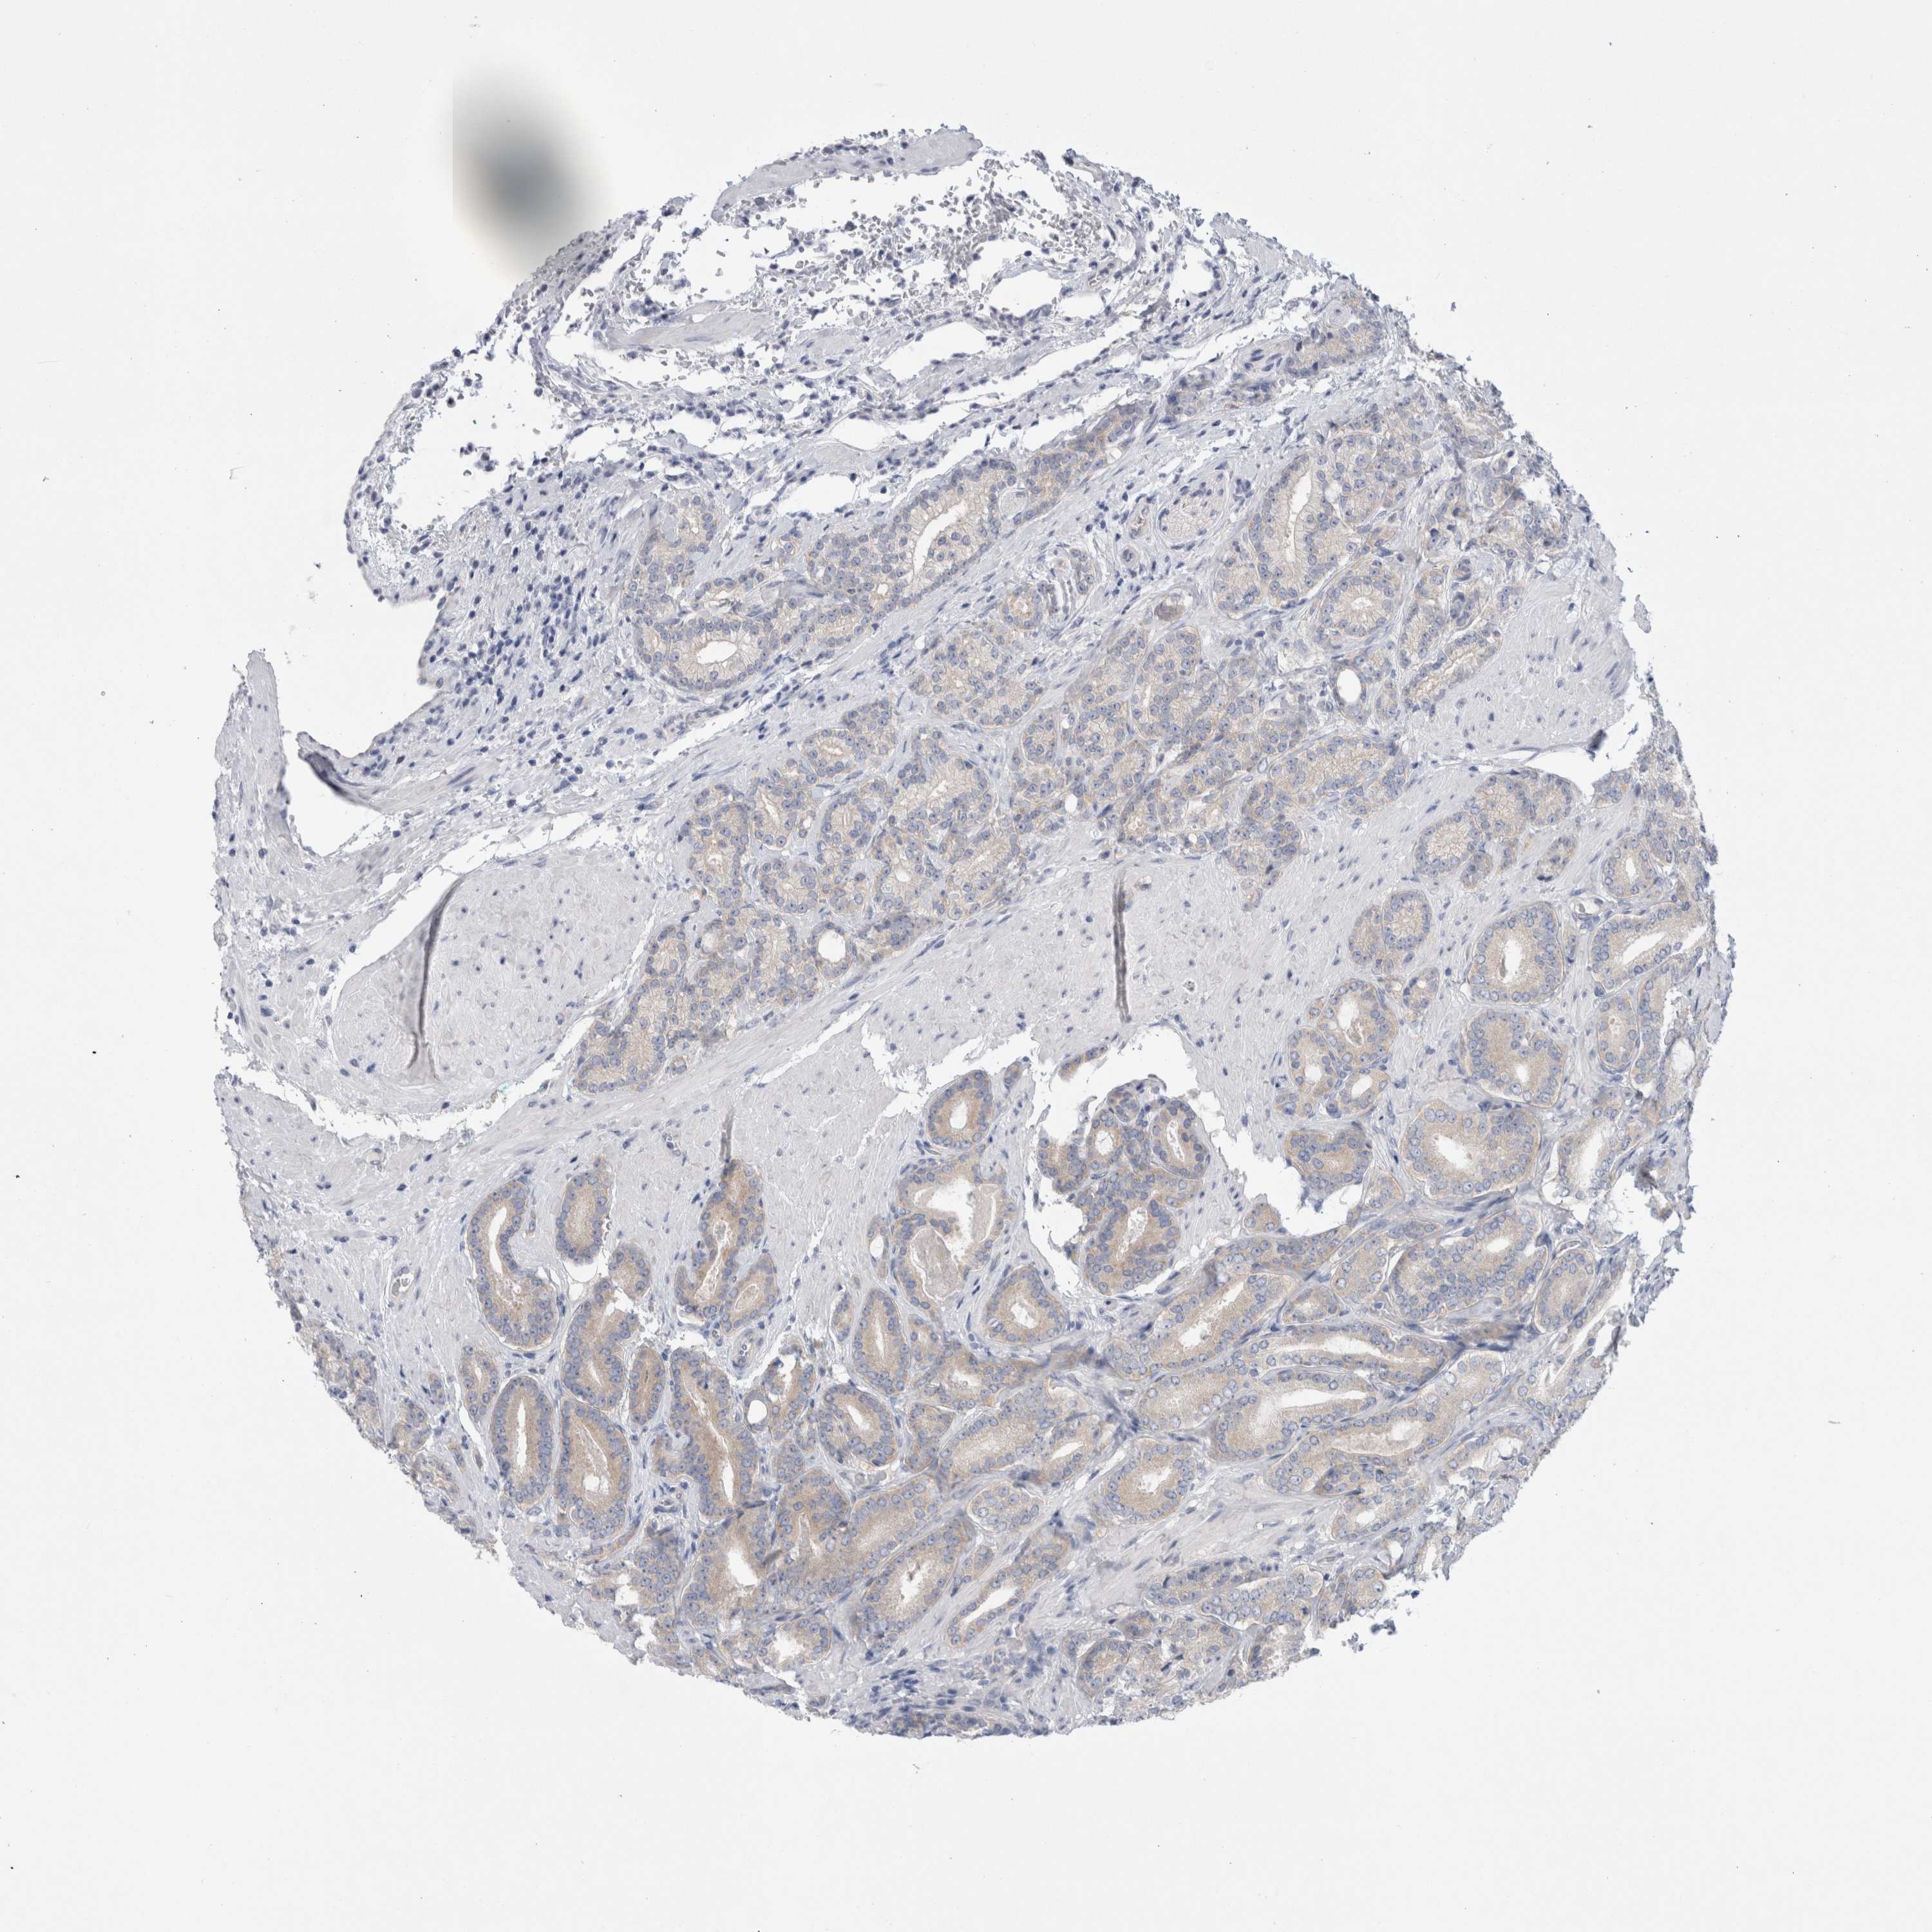

PROSTATE CANCER - Protein expressioni

A mouse-over function shows sample information and annotation data. Click on an image to view it in a full screen mode. Samples can be filtered based on level of antibody staining by selecting one or several of the following categories: high, medium, low and not detected. The assay and annotation is described here.

Antibody stainingi

Antibody staining in the annotated cell types in the current human tissue is reported as not detected, low, medium, or high, based on conventional immunohistochemistry profiling in selected tissues. This score is based on the combination of the staining intensity and fraction of stained cells.

Each image is clickable and will lead to virtual microscopy that enables deeper exploration of all samples and also displays staining intensity scores, fraction scores and subcellular localization as well as patient and tissue information for each sample.

Antibody HPA024000

Antibody HPA024001

Antibody HPA024467

Staining

High

Medium

Low

Not detected

Intensity

Strong

Moderate

Weak

Negative

Quantity

>75%

75%-25%

<25%

None

Location

Nuclear

Cytoplasmic/membranous

Cytoplasmic/membranous,nuclear

Adenocarcinoma, High grade

Adenocarcinoma, Low grade